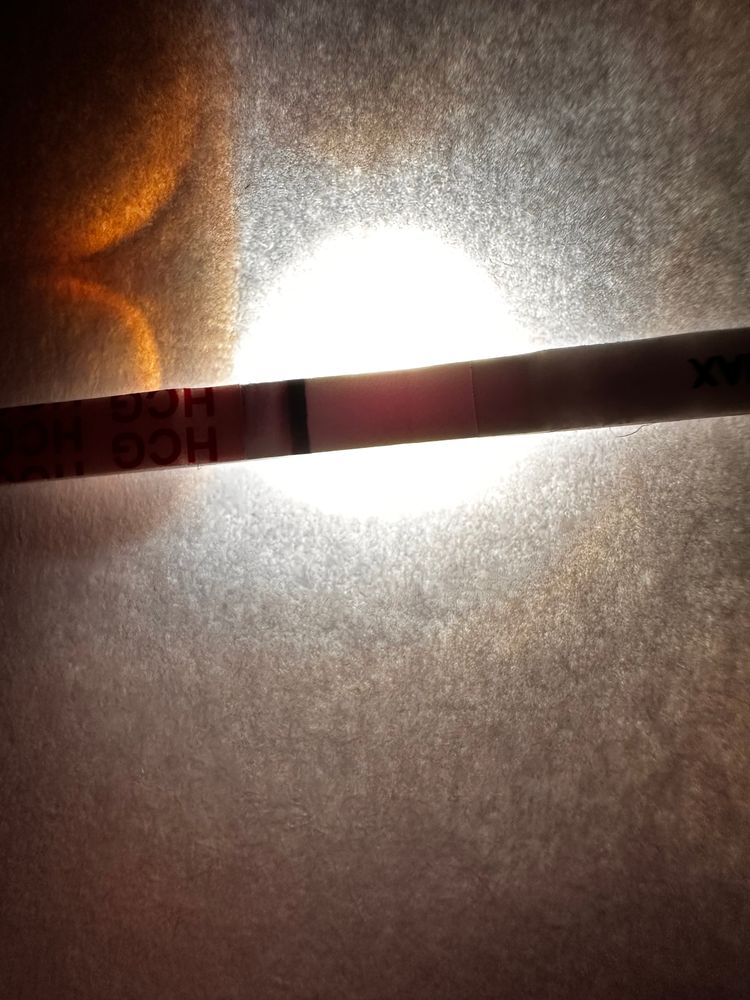

Девачки, почитала всех и короче пошла тесто манить , не могу уснуть теперь 😂😂😂😂 во что получилось напоминаю на 6 дпо

тест на о сегодняшний

Тест с верху старый 2 цикла назад

у меня в беременность именно тесты на овуляцию показали жирные // , сделала тест на б и была еле заметная полоска . Сейчас прикреплю . Но к сожалению замерла на 6 Нед

а тесты на овуляцию уменьшались после овуляции? Или тоже оставались насыщенными?

Алина Горева, прям сразу после овуляции? Такие жирные как у меня после 01.02? Или жирнее?)